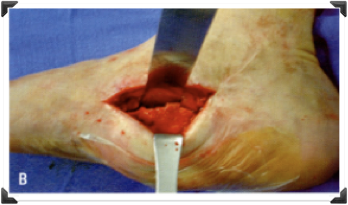

Tratamiento

• Ninguno

• Conservador ?

• Quirúrgico ?

• Anestesia ?

• Fijacion Interna ?

• Inmovilizacion ?